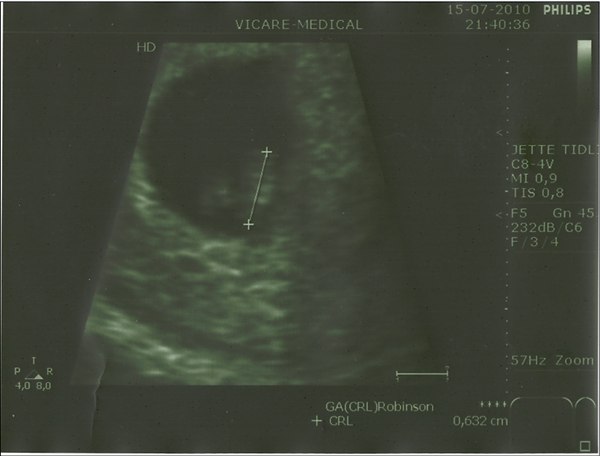

Har lige været til scanning, og hvor var det stort, en ting var første gang, men fik både set hjerteblinkende og hørt det lille hjerte slå, hvor var det fantastisk

Det bedste er at selvom der er vej til uge 12, hvor de siger man er mere sikker, mente hun risikoen var minimal, da jeg jo nu gennem 2 scanninger ( 5+6 og 6+6 ) har ste det hele sidder som det skal, og barnet vokser som det skal, og vi har set og hørt hjertelyden, så det er bare super dejligt